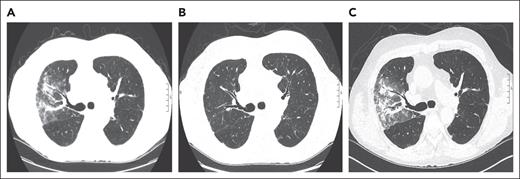

A 73-year-old man with a history of myelodysplastic syndrome, who received a nonmyeloablative allogeneic peripheral blood stem cell transplant (PBSCT), presented with progressive dyspnea, a nonproductive cough, and hypoxemia a year after HCT. Weeks before presentation, the patient was newly diagnosed with cGVHD of the skin. A chest computed tomography (CT) scan showed upper lobe predominant ground-glass opacities in a subpleural and peribronchovascular distribution (Figure 1A). The patient was treated for infectious pneumonia with levofloxacin without improvement. Clinical history did not reveal an antecedent exposure to medications associated with OP. Bronchoscopy with bronchoalveolar lavage (BAL) was performed, and microbiology culture results for bacterial, fungal, and viral pathogens were negative. On the basis of a lack of association with known pulmonary toxic medications or infectious agents, HCT-OP was diagnosed, and prednisone (1 mg/kg per day) was initiated with a slow taper over 4 months. The patient’s clinical symptoms rapidly resolved, including his skin cGVHD, and radiological improvement was achieved (Figure 1B).

Figure 1.

Representative coronal images from a noncontrast chest CT scan. (A) CT scan of the chest, demonstrating a right-sided upper lobe–predominant, peripheral ground-glass opacity at the diagnosis of organizing pneumonia. (B) CT images after 4 months of treatment with prednisone, demonstrating resolution of opacities.